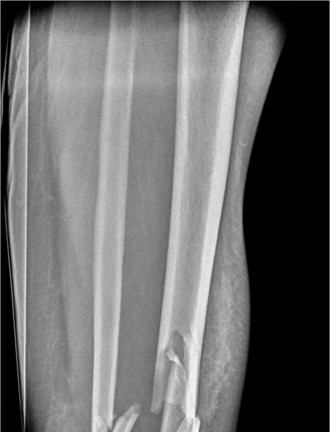

You are called to the emergency department to evaluate the right arm of a 26-year-old female who fell approxi…